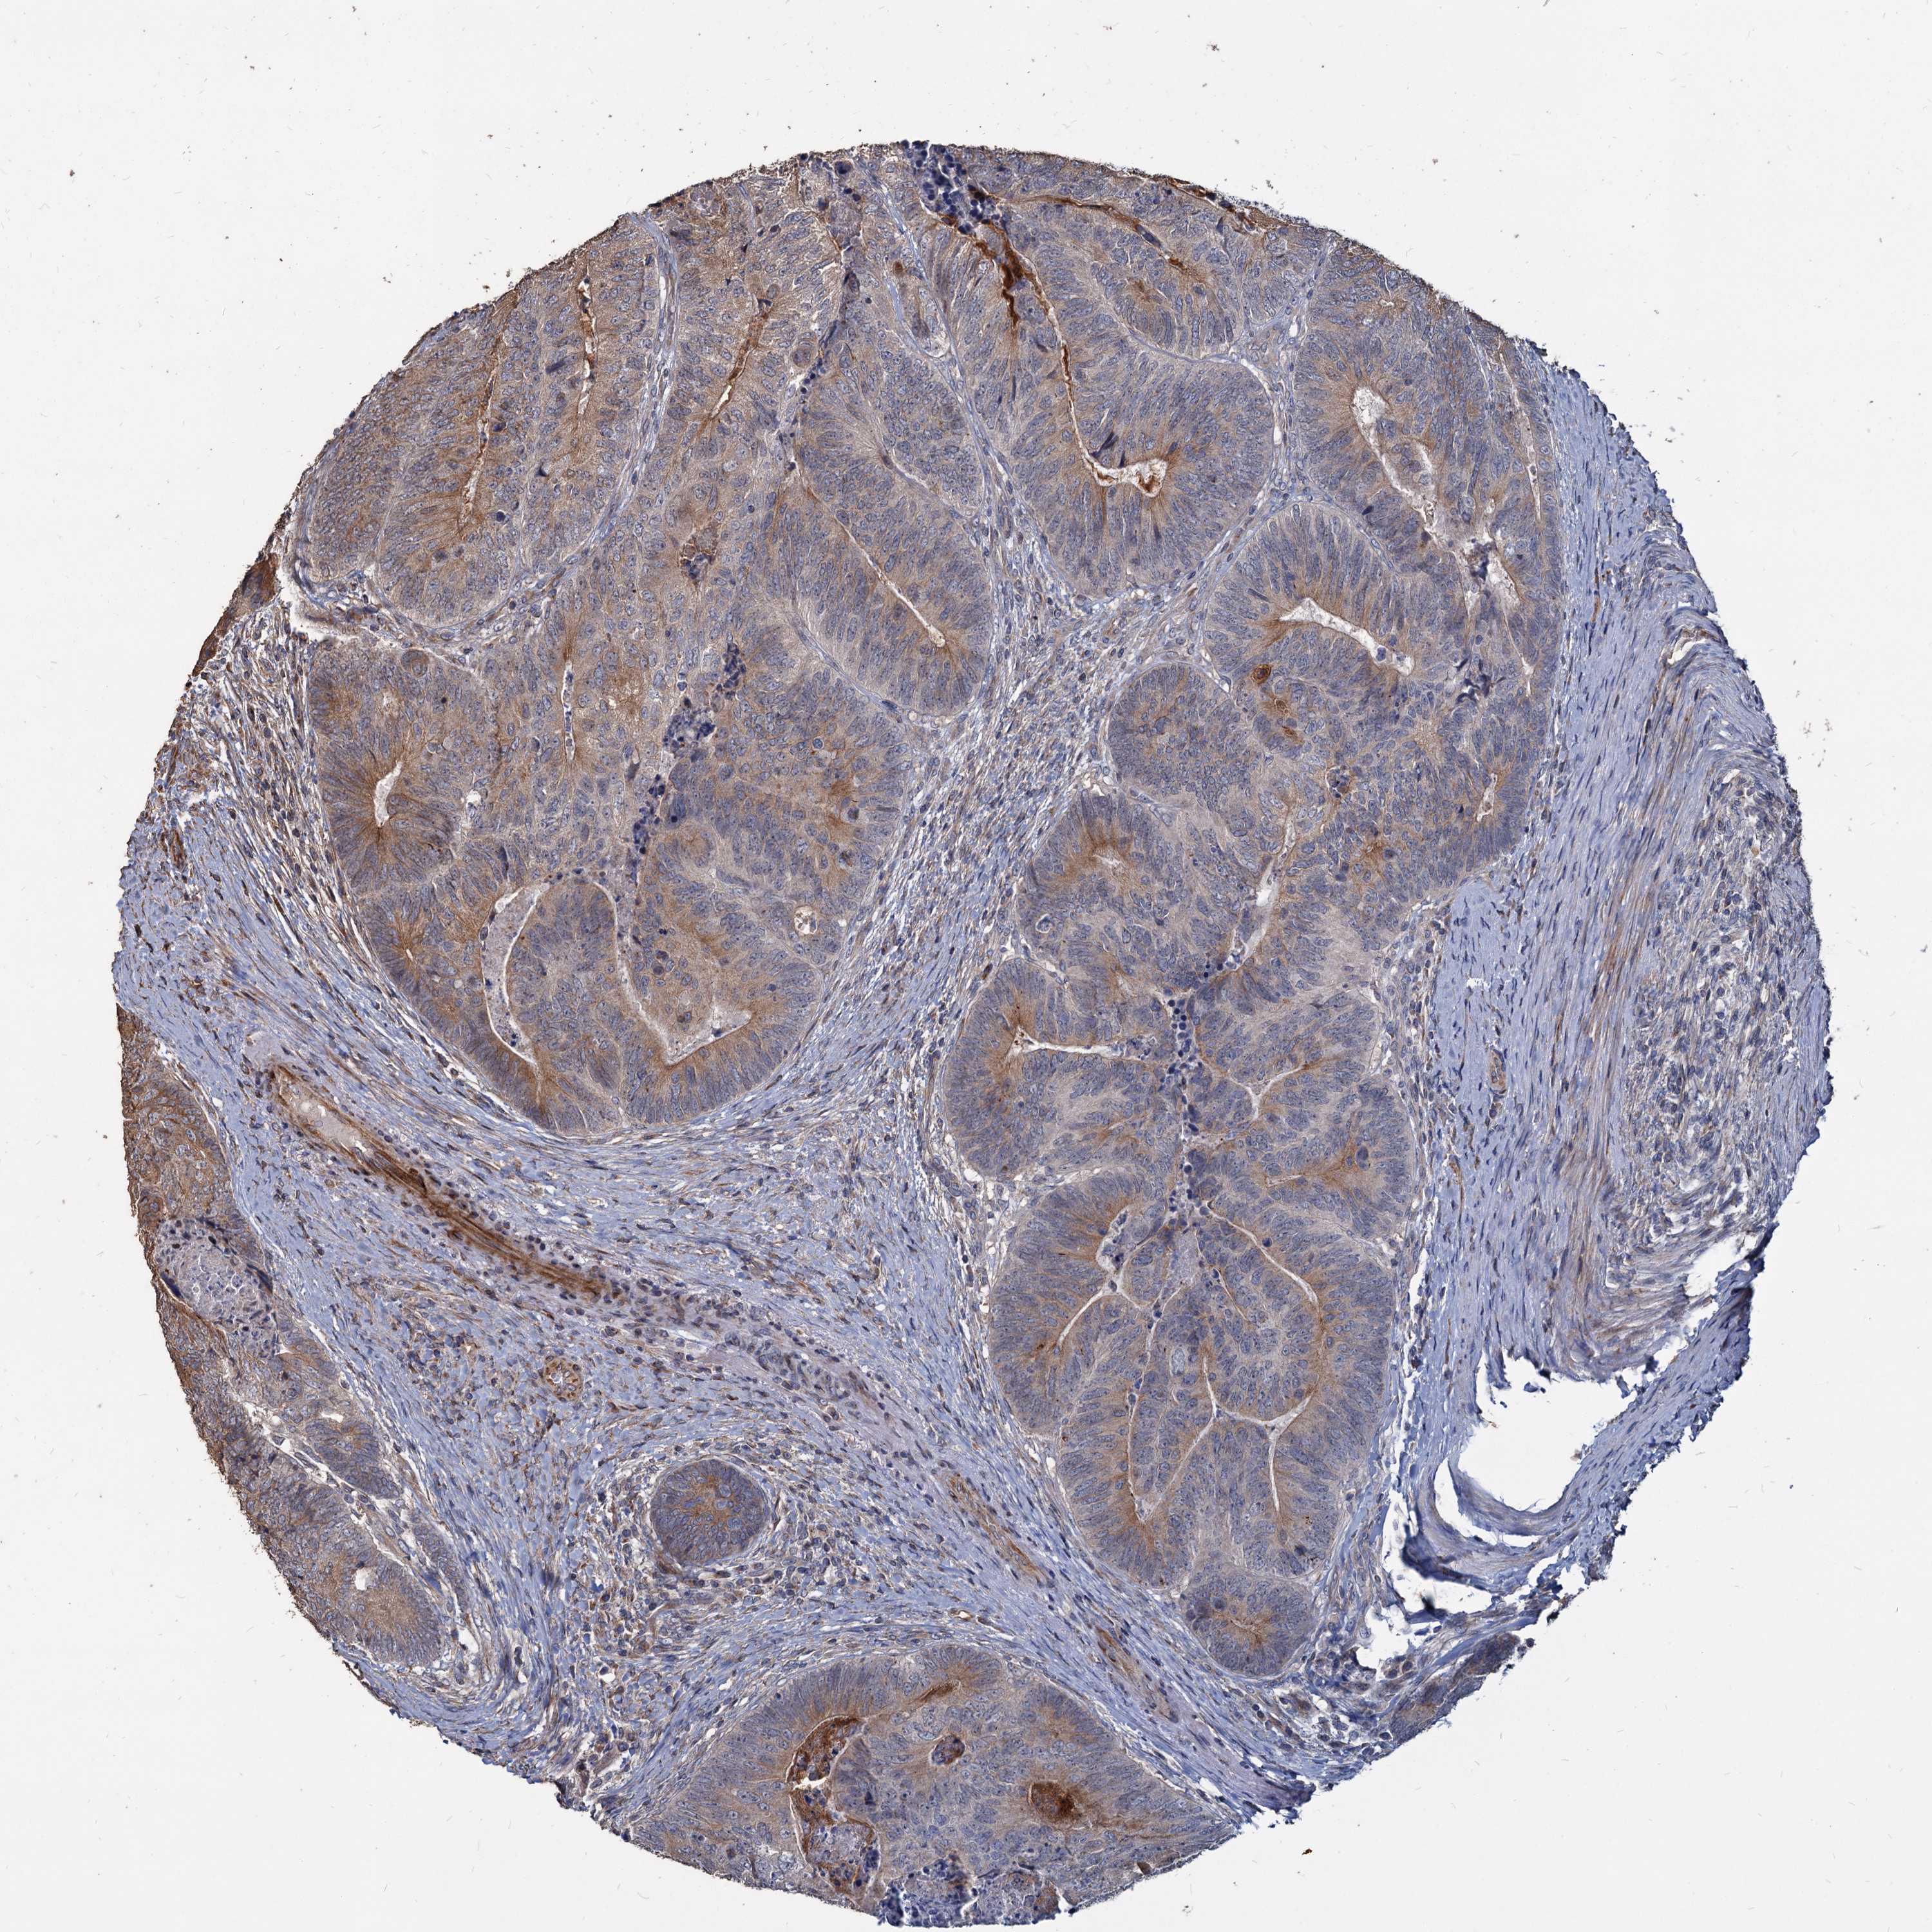

CANCER COLORECTAL CANCER Show tissue menu

ANTIBODIES

AND

VALIDATION

Colorectal cancer

Human cancer

Colon adenocarcinoma